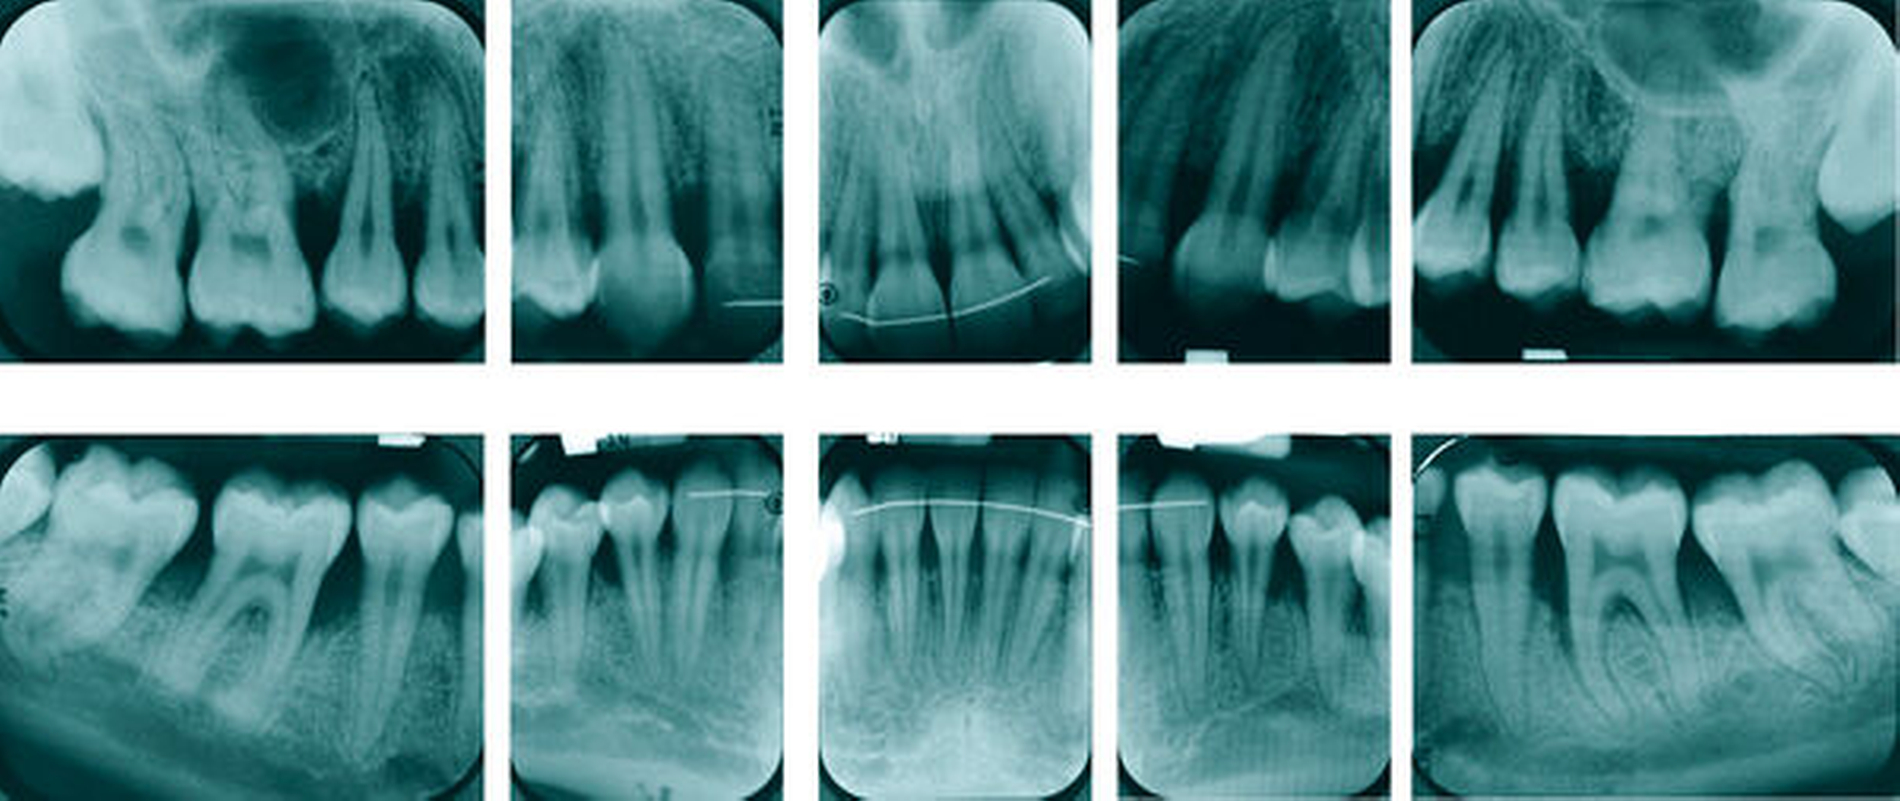

Die subgingivale Instrumentierung hat zum Ziel, durch die Entfernung harter und weicher Beläge von der Wurzeloberfläche die Weichgewebsentzündung zu reduzieren. Eine Zielgröße der Behandlung ist „Pocket Closure“ (geschlossene Taschen), was als Taschensondierungstiefe (TST) ≤ 4 mm und Abwesenheit von Bluten auf Sondieren (BOP) definiert ist. Ein RCT mit 169 Patienten mit einem dreimonatigem Follow-up und weitere elf prospektive Studien (n = 258) mit einem sechsmonatigem Follow-up wurden analysiert. Erfasst wurden die postoperative Reduktion der TST (primäre Zielgröße) und der prozentuale Anteil von geschlossenen Taschen (sekundäre Zielgröße). Die Evidenz zeigte eine durchschnittliche Reduktion der TST von 1,7 mm nach sechs Monaten, einen mittleren Anteil an geschlossenen Taschen von 74 Prozent und eine durchschnittliche Reduktion des BOP um 63 Prozent. Tiefere Taschen (> 6 mm) zeigten eine größere mittlere Reduktion der Taschensondierungstiefe von 2,6 mm (Abbildung 2).

Es gibt eine Vielzahl an Instrumenten für die subgingivale Instrumentierung (Abbildung 3). Es wurden vier RCTs (n = 132) identifiziert. Die Ergebnisse wurden nach 6/8 Monaten für TST-Reduktion (primärer Endpunkt) und Gewinn an klinischem Attachmentniveau (CAL, sekundärer Endpunkt) bewertet. Die Evidenz zeigte keine klinisch relevanten oder statistisch signifikanten Unterschiede zwischen der Instrumentierung mit verschiedenen Instrumenten. Die Ergebnisse wurden als stark und konsistent bewertet.

Die subgingivale Instrumentierung wurde traditionell in mehreren Sitzungen (das heißt quadrantenweise) durchgeführt. Alternativ wurden sogenannte „Full-Mouth“-Protokolle vorgestellt. Diese beinhalteten ein- und zweizeitige Therapien innerhalb von 24 Stunden. Diesem Ansatz liegt die Überlegung zugrunde, dass bei einer zeitlich komprimierten Vorgehensweise das Risiko einer Reinfektion der instrumentierten Taschen durch parodontalpathogene Mikroorganismen aus den noch nicht instrumentierten Taschen vermindert werden könnte (Abbildung 4). Protokolle, die Antiseptika beinhalteten (Full-Mouth-Disinfection), wurden in der Analyse von Suvan et al. [2020] nicht berücksichtigt. Eingeschlossen wurden acht RCTs (n = 212) mit einem Follow-up von ≥ 6 Monaten. Die Zielgrößen waren TST-Reduktion (primärer Endpunkt), Gewinn an klinischem Attachment (CAL), BOP-Reduktion und Pocket Closure (sekundäre Endpunkte). Es wurden keine deutlichen Unterschiede zwischen beiden Therapiemodalitäten festgestellt. Die Evidenz wurde als stark und konsistent bewertet. Die Ergebnisse bestätigen eine aktuelle Cochrane-Übersicht [Eberhard et al., 2015].